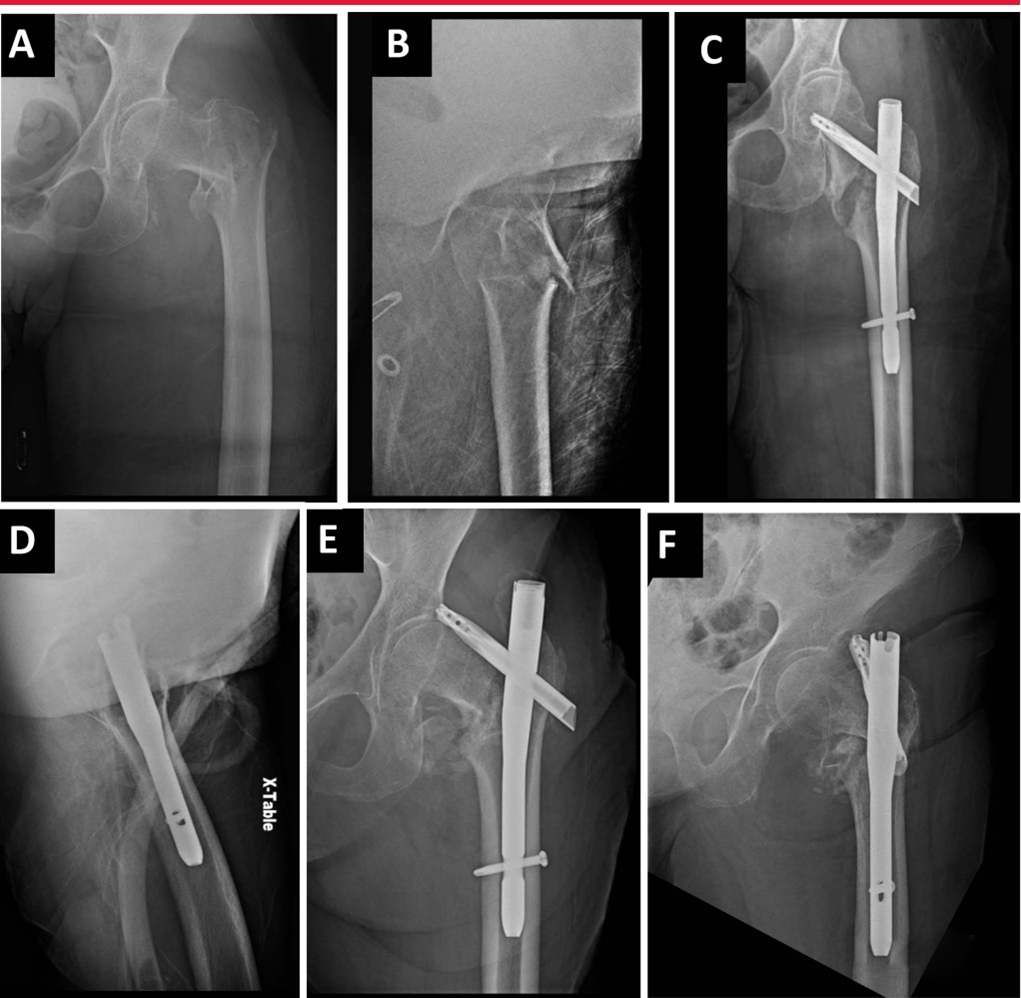

Интрамедуллярное лечение межвертельного перелома бедренной кости – 8 аспектов оптимизации интрамедул

Межвертельные переломы являются распространенной ортопедической травмой, которая влечет за собой значительную заболе···